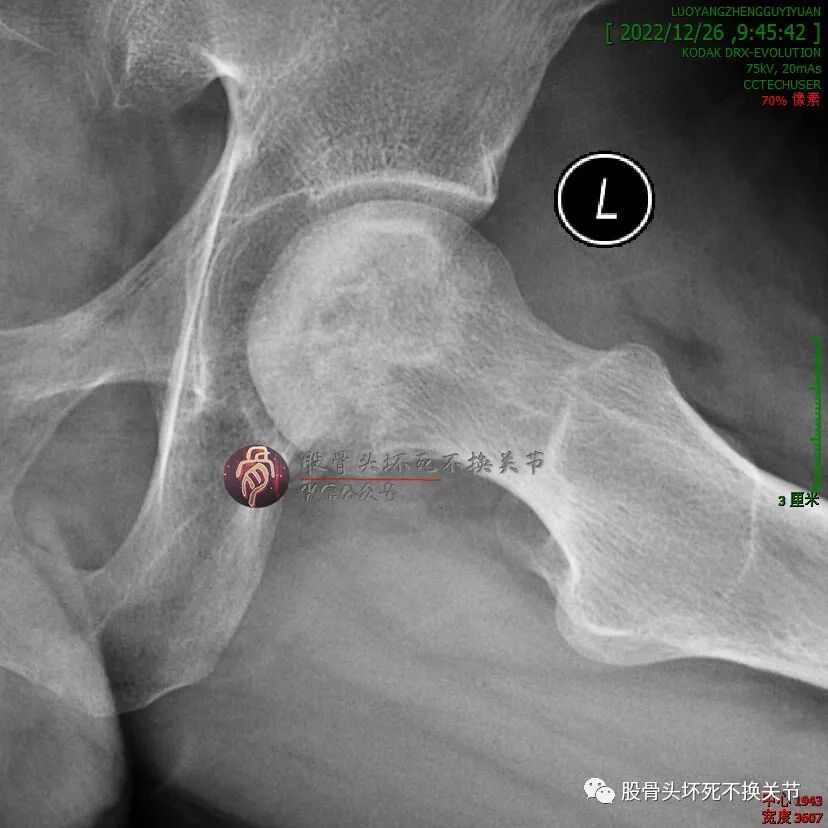

但是,疼痛缓解给予病人莫大希望,开始定期门诊治疗(不用住院、随治随走那种),半年后复查:

这次复查比初次就诊时明显好转,骨密度明显提高,疼痛基本全无,恢复一般的生活、工作能力。